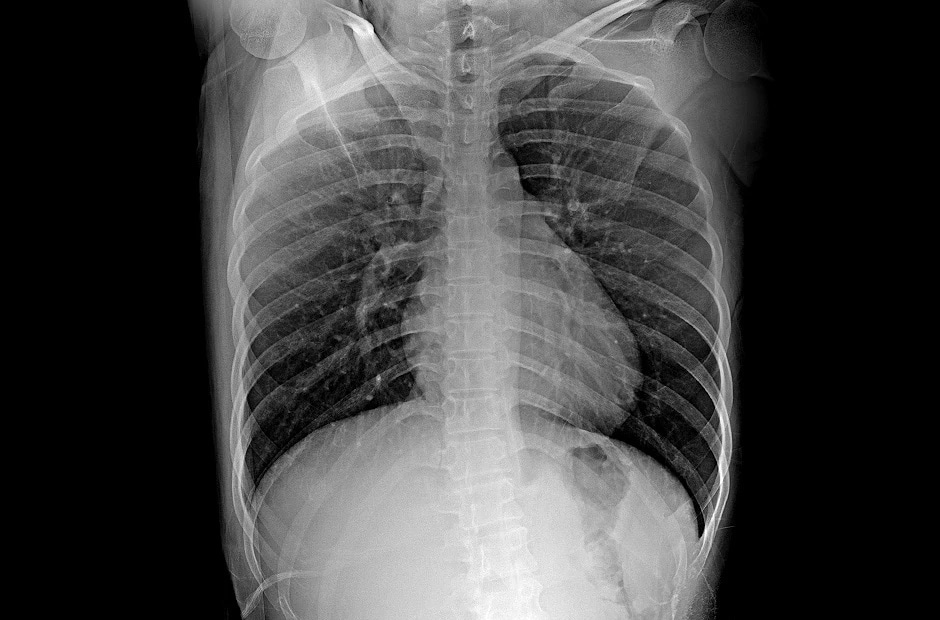

Detector de Rayos X Digital (DXD)

Detector de Rayos X Digital (DXD)

Características clave

- Tamaño del Pixel de 140㎛ y Conversión A/D de 16 Bits

- Imagen en Bruto en 2.5s (Inalámbrica) y 2s (por Cable)

- Modo AP y Almacenamiento Automático en DXD

- IP53: A Prueba de Agua y A Prueba de Polvo

- Cuerpo de Magnesio y Fibra de Carbono

- Software de Adquisición de la Estación de Trabajo LG

Galería